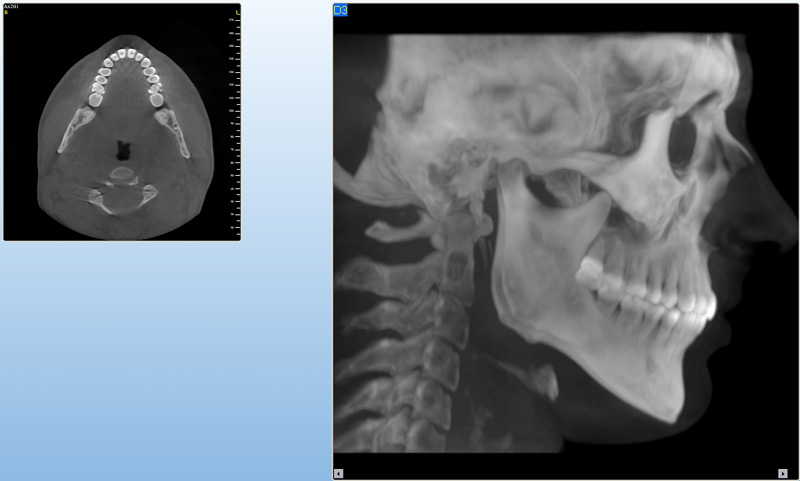

NewTom Giano

Jedná se o nejnovějším přístroj ze skupiny dentálních hybridních CBCT (3D) + 2D (pan i ceph) systémů. Opět umožňuje na základě jediného snímkování vytvořit všechny typy RTG zobrazení, které jsou pro lékaře potřebné. Používaná technologii tzv. „kuželového paprsku“ a speciální senzory pro minimální zátěž při snímkování pacienta.

Vyšetření pomocí tohoto přístroje (nebo 3D DVT - NewTom) a získaná data používáme pro každou implantaci, dále ve stomatochirurgii (zlomeniny čelistí, zuby moudrosti, cysty, onemocnění čelistního kloubu), ortodoncii (retinované zuby, nadpočetné zuby), parodontologii atd.